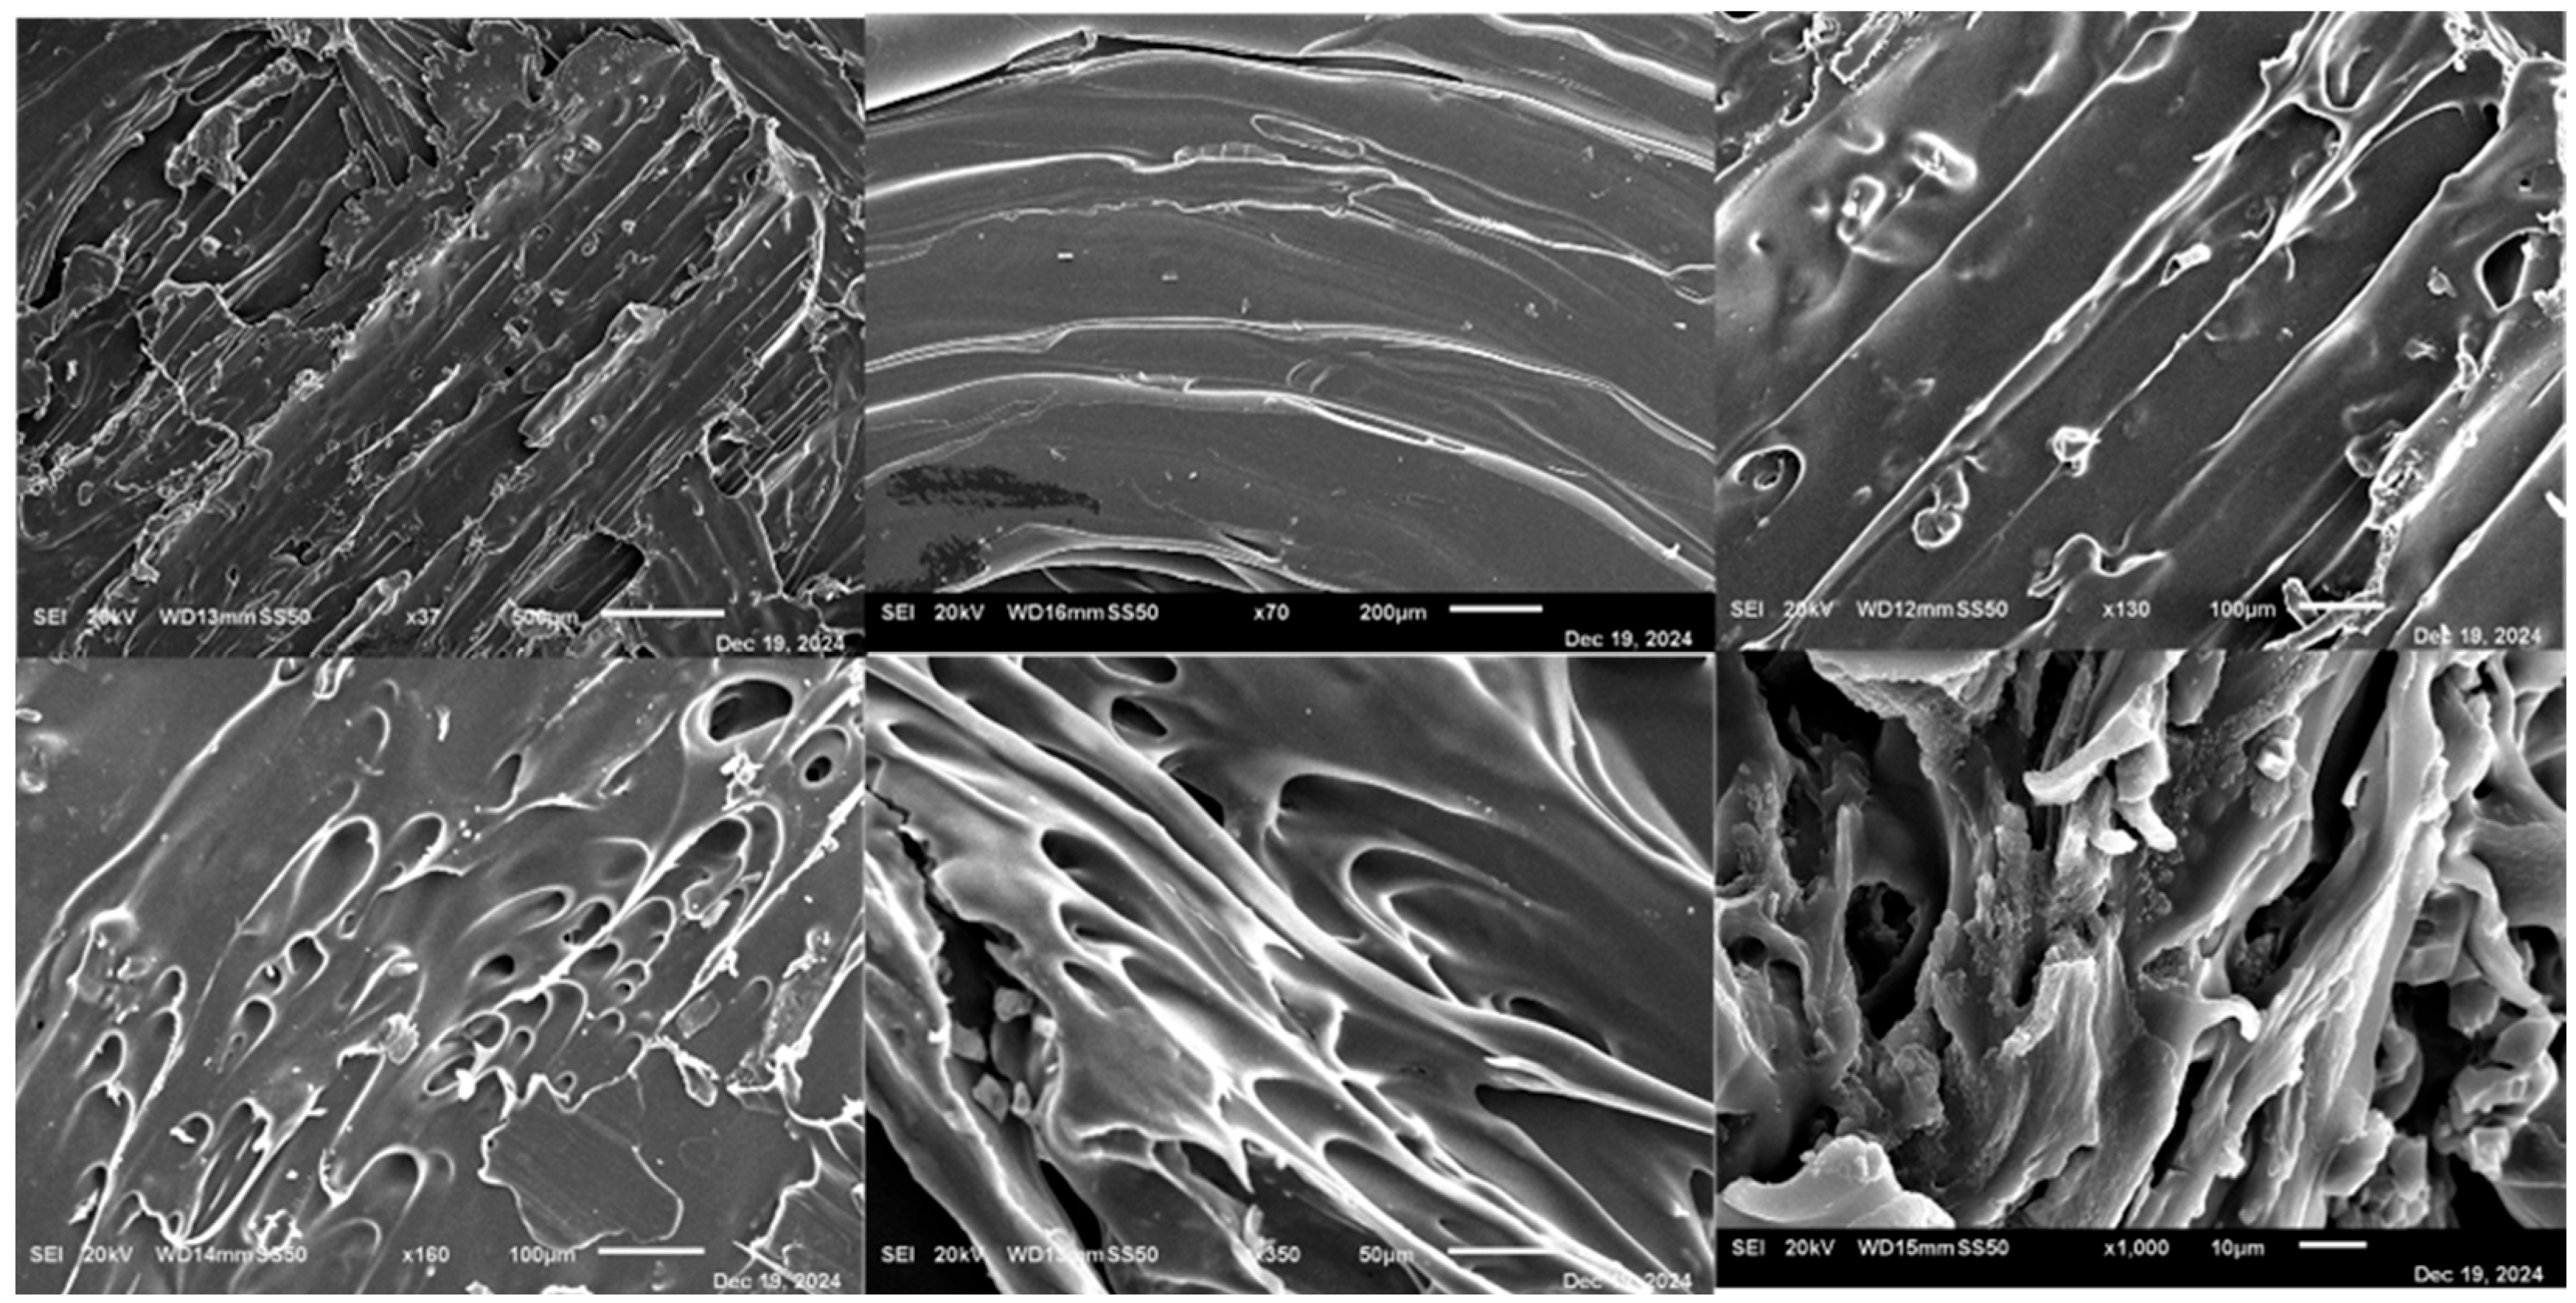

3.15. Scanning Electron Microscopy (SEM)